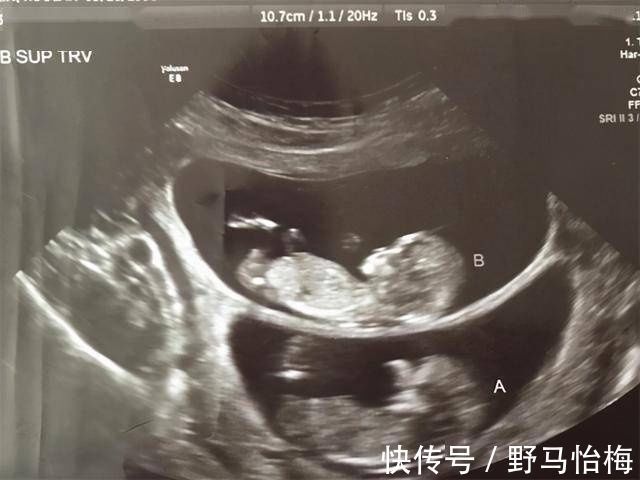

b超|孕妇做B超时,医生总是说胎儿比实际天数多几天是为什么?

【 b超|孕妇做B超时,医生总是说胎儿比实际天数多几天是为什么?】导读:到了怀孕的孕中晚期的时候,孕妈们在产检的时候对于B超应该是再熟悉不过的了,从第一次看见小宝宝的成像那种惊喜激动,到后面懂得去关注胎儿具体的发展情况。妈妈们对于B超的最大反应大概就是:我的孩子有没有什么异常的情况?

所以,孕妈们在产检的时候,最怕出现的就是有不一样的检查结果发生,有的孕妈在做B超的时候,总是会冷不丁地听到医生对着B超结果说上一句:XX偏大一周。于是,孕妈听完之后就会变得很紧张,偏大一周是怎么回事?是宝宝有什么问题吗?

其实,孕妇做B超时这种情况是经常发生的,而医生总说胎儿的检查结果显示要比实际天数多几天是为什么?